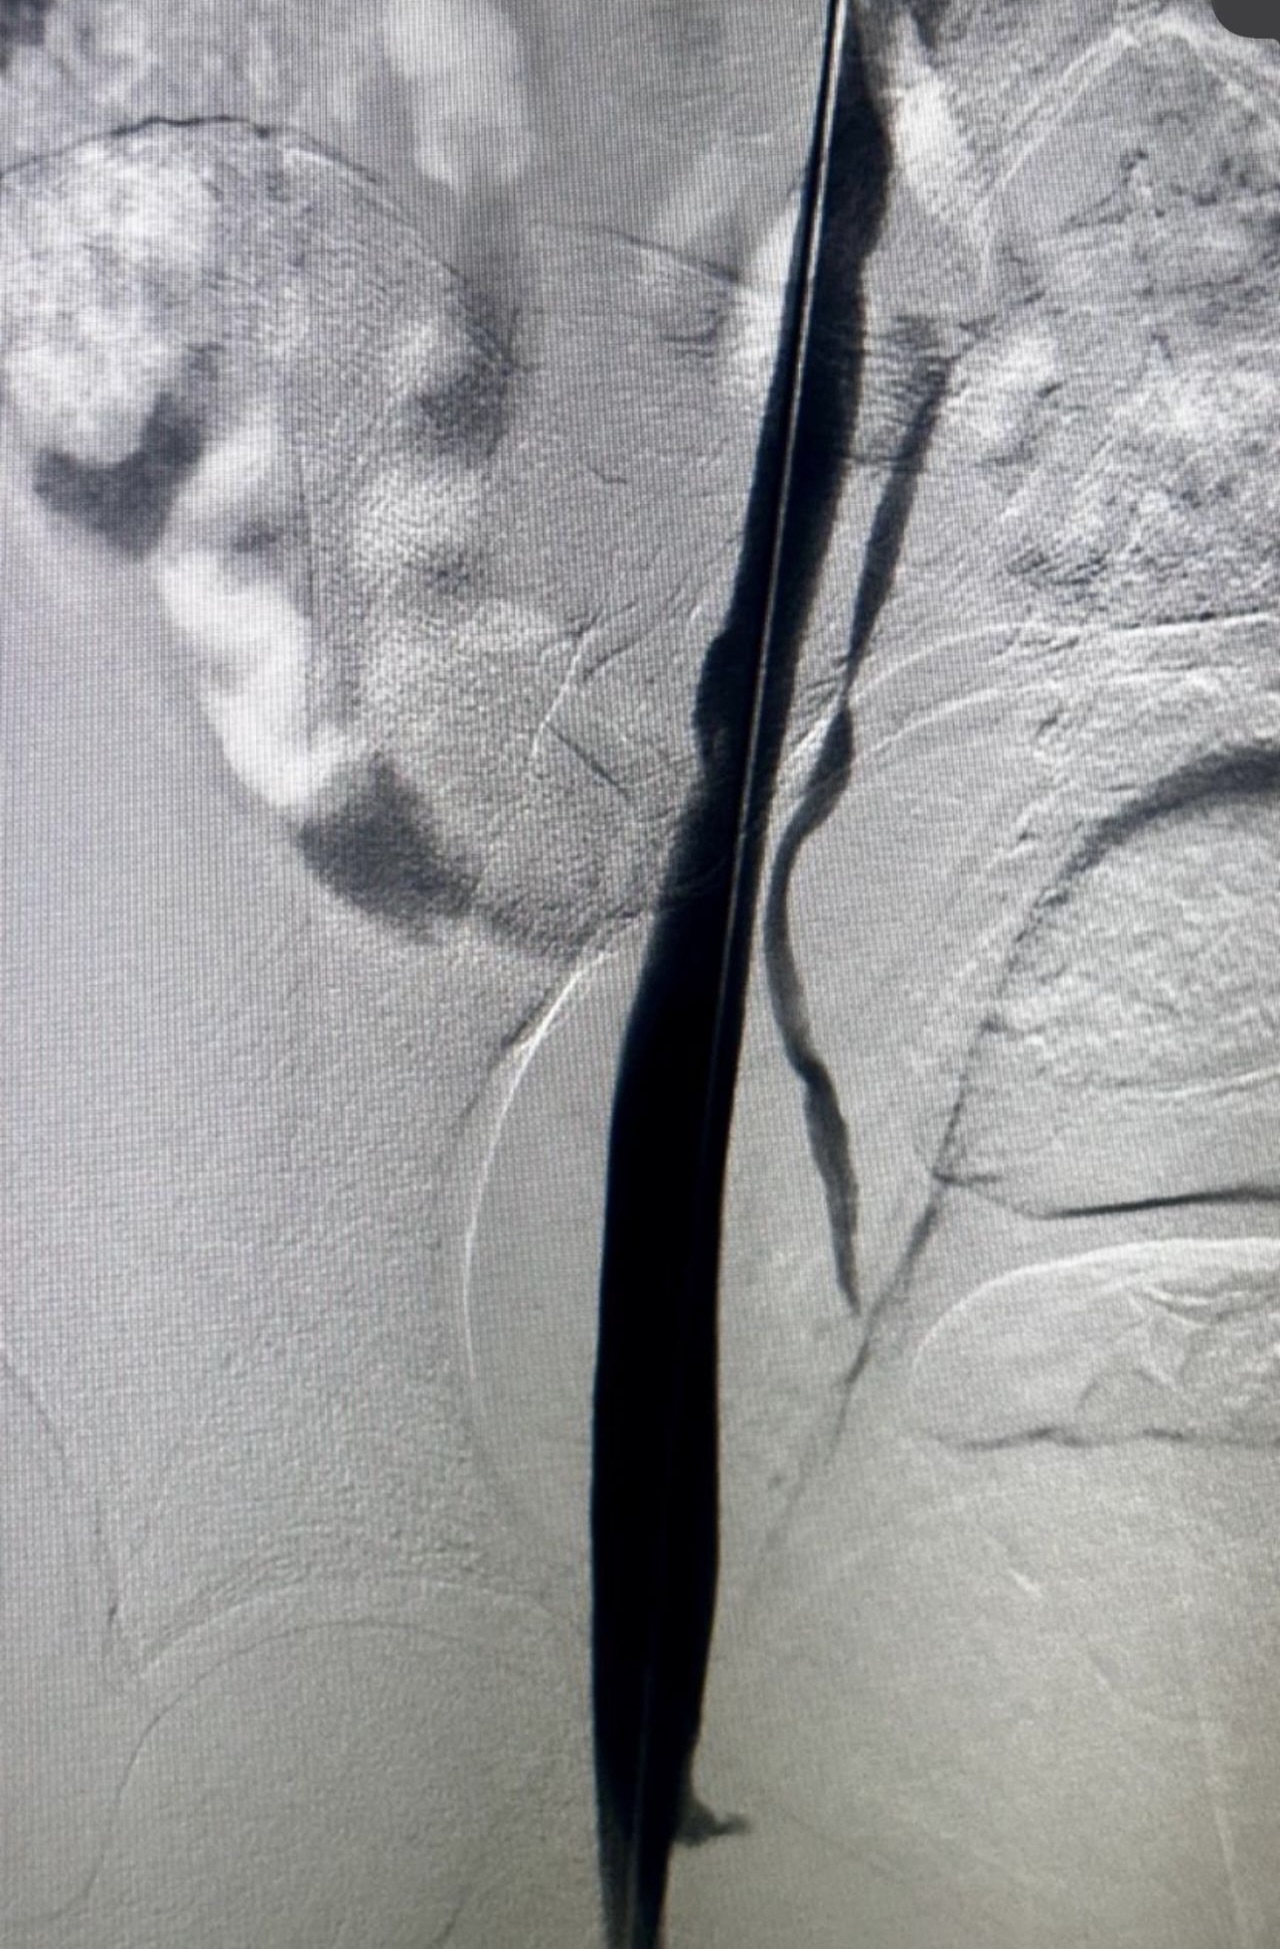

”Rapid Revascularization for Iliofemoral DVT

Acute extensive iliofemoral DVT demands a definitive solution.

The Case: Complete occlusion of the right iliac and femoral veins.

The Procedure:

1. Transpopliteal Access for direct control.

2. Mechanical Thrombectomy using the Penumbra 16 catheter for rapid clot aspiration.

3. Adjunctive Balloon Angioplasty to address underlying venous stenoses and ensure a durable result.

The Outcome: Immediate restoration of flow, resolution of symptoms, and a significant reduction in the risk of Post-Thrombotic Syndrome.

A powerful, minimally invasive approach that changes the patient’s trajectory.”